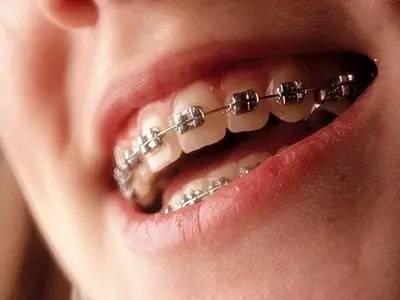

牙套的种类:金属托槽矫正

技术特点:

价格便宜,绝大多数人群都可以采用这种托槽来进行矫正。

材料优质,具有金属刚性及弹性,不易断裂变形。

舒适稳固,独特自然的弯曲程度,提供大限度的接触面和舒适度。

矫正效果好,缩短复诊次数、调节疗程,且性能基本达到使用要求。

传统矫正方法,历史悠久,价格低廉。